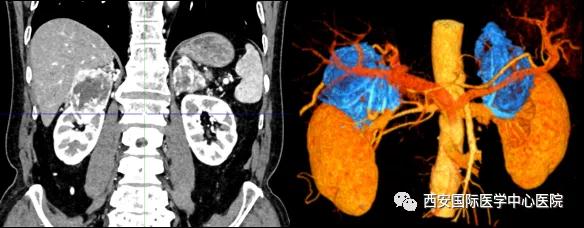

7月15日,西安國(guó)際醫(yī)學(xué)中心醫(yī)院泌尿外科楊增悅教授團(tuán)隊(duì)成功完成“機(jī)器人輔助根治性右腎、右腎上腺部分切除 左腎上腺切除 腎門淋巴結(jié)清掃術(shù)”。此臺(tái)手術(shù)涉及三個(gè)器官:右腎切除、右側(cè)腎上腺轉(zhuǎn)移瘤切除(保留部分正常腎上腺組織)、左腎上腺切除,并且清掃了腎門淋巴結(jié)。

今年七十五歲的患者,來(lái)自陜西省商洛市,四月前因腰背部疼痛就診于當(dāng)?shù)蒯t(yī)院,行CT檢查發(fā)現(xiàn)“右腎、雙側(cè)腎上腺占位,前縱膈淋巴結(jié)腫大,雙肺多發(fā)結(jié)節(jié)、胸椎骨質(zhì)破壞,考慮轉(zhuǎn)移瘤”。為進(jìn)一步診斷治療,患者的兒子帶他來(lái)到西安某三甲醫(yī)院,查泌尿系CT提示“右腎占位性病變,多考慮腎癌,雙側(cè)腎上腺多發(fā)轉(zhuǎn)移灶,腹膜后多發(fā)腫大淋巴結(jié)”;行穿刺活檢提示“腎透明細(xì)胞癌”;并給予患者口服靶向藥物的治療方案。

手術(shù)由楊增悅教授主持,舒濤主治醫(yī)師、王東主治醫(yī)師主刀,黃怡醫(yī)師、王平醫(yī)師協(xié)助完成。由于第四代達(dá)芬奇機(jī)器人更加靈活和精準(zhǔn)的特性,手術(shù)全程順利,尤其是完全精準(zhǔn)的“解鎖”了右腎動(dòng)脈和右腎靜脈的數(shù)十根交互纏繞的分支血管。術(shù)后患者麻醉恢復(fù)后生命體征平穩(wěn),順利返回泌尿外科普通病區(qū)進(jìn)一步康復(fù)。